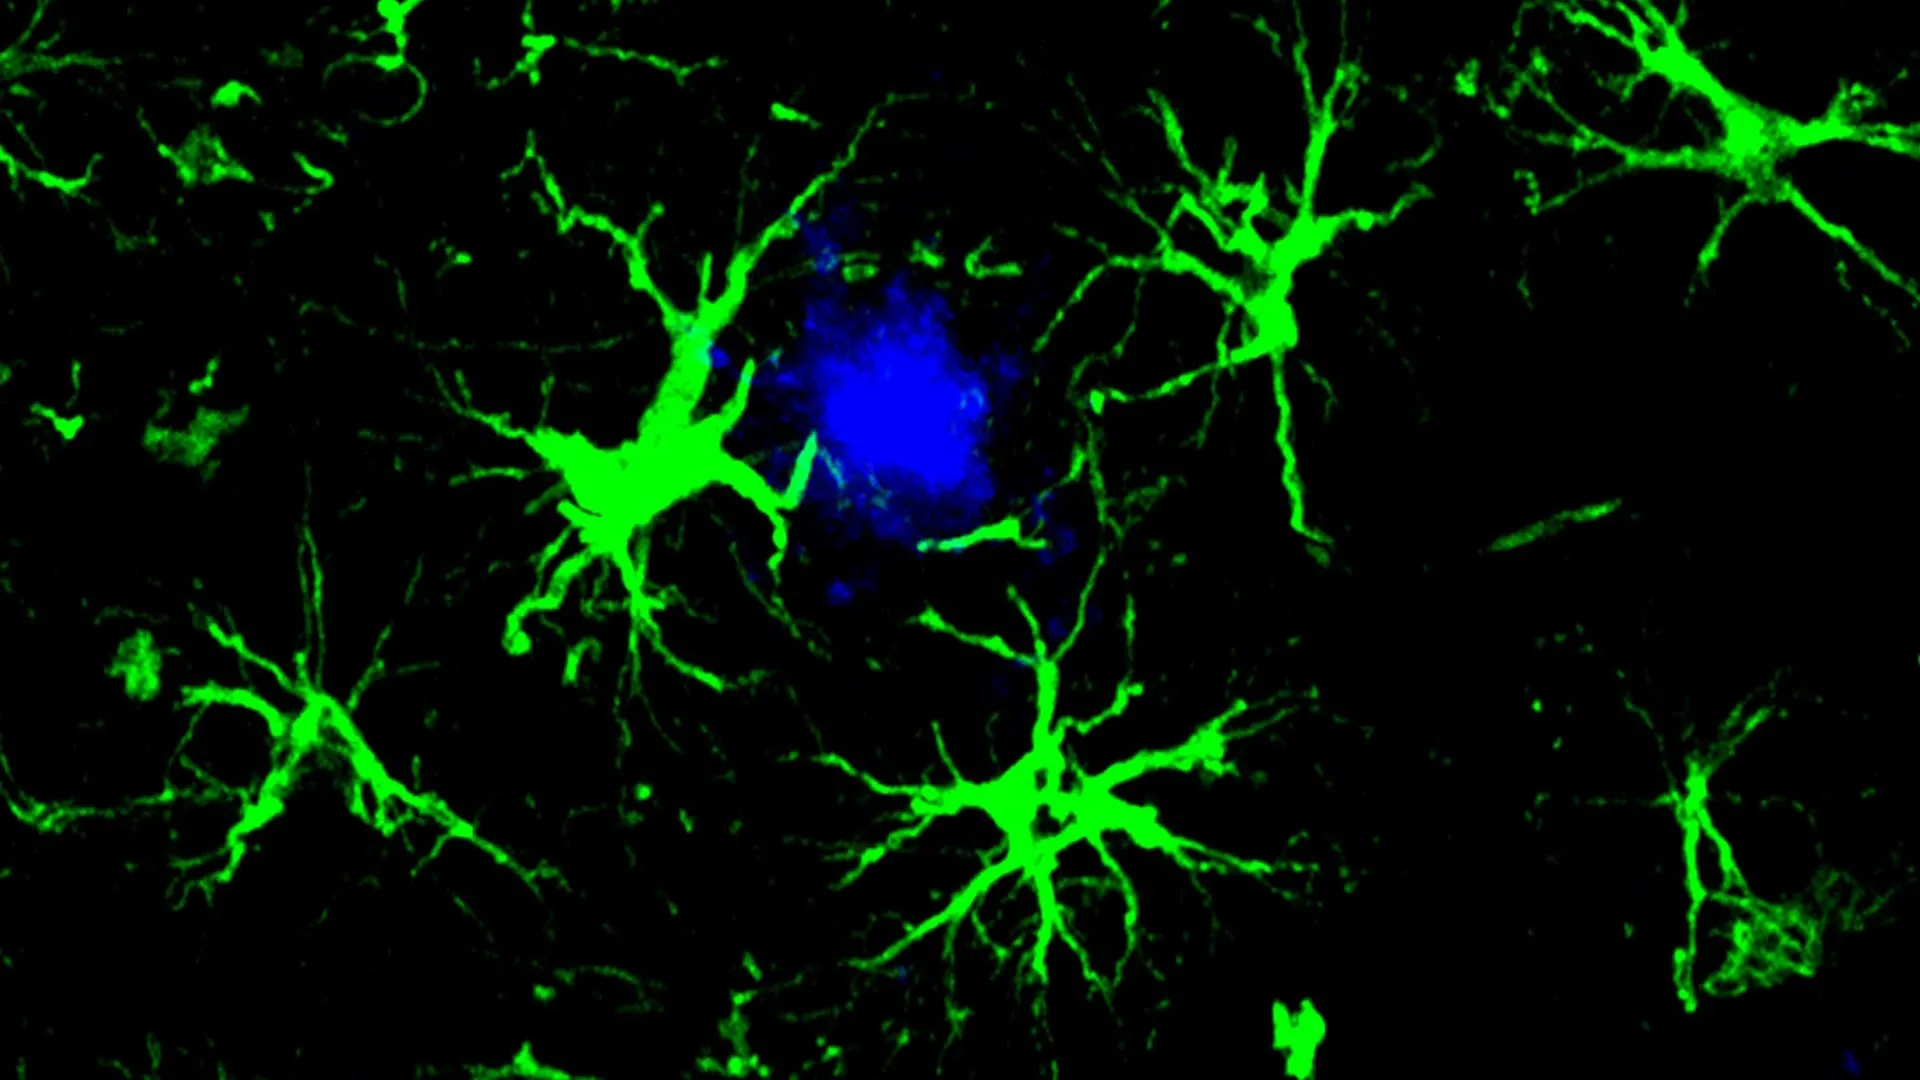

A nova estratégia é inspirada nas terapias CAR-T usadas no tratamento do câncer. Nessas terapias, células T do sistema imunológico são geneticamente modificadas para identificar e atacar células cancerígenas. Neste enfoque para Alzheimer, os cientistas modificaram um tipo diferente de célula. Eles equiparam astroctócitos, um tipo comum de célula do cérebro, com um dispositivo de homing CAR que permite às células se fixarem em alvos específicos e destruí-los.

Esses CAR-astroctócitos projetados atuam como poderosas células de limpeza no cérebro. Seu design permite que eles localizem e removam proteínas prejudiciais que contribuem para o declínio cognitivo.

Para reduzir a carga sobre as microglia, o primeiro autor Yun Chen, PhD, então estudante de pós-graduação trabalhando nos laboratórios de Colonna e David M. Holtzman, MD, Professor Distinto de Neurologia da WashU Medicine, focou nos astroctócitos. Os astroctócitos são as células mais abundantes no cérebro e normalmente ajudam a manter um ambiente saudável para os neurônios.

Chen redesenhou os astroctócitos para se tornarem células especializadas em remoção de amiloide. Ele introduziu um gene que produz um receptor de antígeno quimérico (CAR) em astroctócitos usando um vírus inofensivo injetado em camundongos. Uma vez expresso na superfície dos astroctócitos, o CAR permitiu que as células capturassem e absorvessem as proteínas beta-amiloide. Com essa habilidade adicional, os astroctócitos se concentraram em remover placas de beta-amiloide em camundongos que são inclinados a desenvolvê-las. Normalmente, os astroctócitos ajudam a manter a ordem no cérebro.